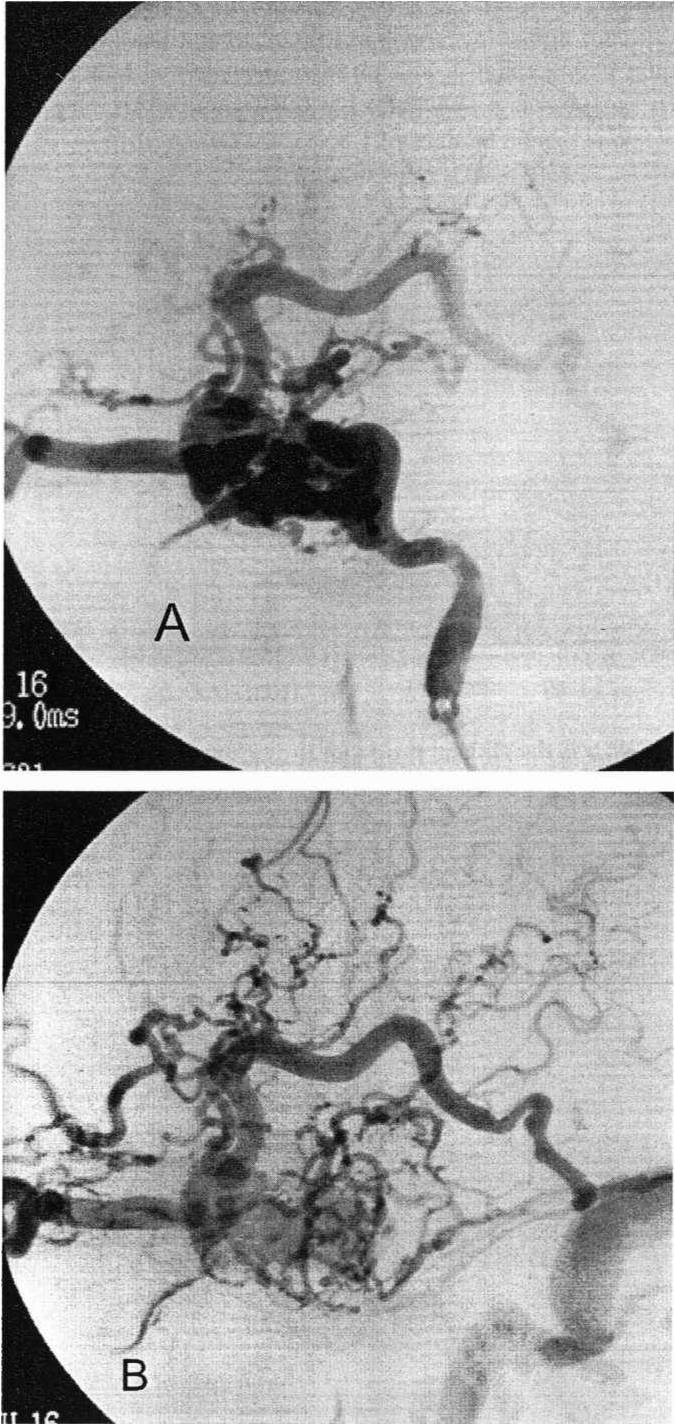

Carotid-cavernous fistulas (CCFs) can be

divided into posttraumatic and spontaneous types. They are

direct shunts between the ICA or ECA and cavernous sinus

and usually occur after trauma or spontaneous aneurysmal

rupture. Traumatic CCFs often present in a delayed fashion;

like spontaneous fistulas, they often present with retro-orbital pain, chemosis, pulsatile proptosis, ocular or cranial bruit,

decreased visual acuity, diplopia, and rarely epistaxis and

subarachnoid hemorrhage. The symptoms depend on the

direction of venous flow and quantity of blood flow through

the fistula. There are four types of GGFs: type A is a direct,

high-flow shunt between the IGA and cavernous sinus (as in this case), and types B to D are low-flow shunts between

the cavernous sinus and meningeal branches of the internal carotid artery, external carotid artery, or both, respectively. Approximately 50% of low-flow fistulas spontaneously

thrombose without treatment. The main treatment option has traditionally included transarterial balloon embolization through the IGA for type A fistulas, although accessing the fistula transvenously (i.e., inferior petrosal sinus) is also commonly performed, especially for indirect types B to D.

A direct surgical approach is indicated if transarterial or transvenous approaches fail. Radiosurgery has been proposed as an option for some of the low-flow fistulas, although it would not be the best strategy for the high-flow symptomatic fistula seen in this patient. Figure A depicts nearly

complete capture of the blood from the internal carotid

artery, and fistulous drainage primarily from the superior ophthalmic and superior petrosal veins. Figure B depicts a later venous run with superior petrosal vein drainage into the transverse-sigmoid sinus junction as well as some venous drainage into the superior sagittal sinus (Kaye and Black,